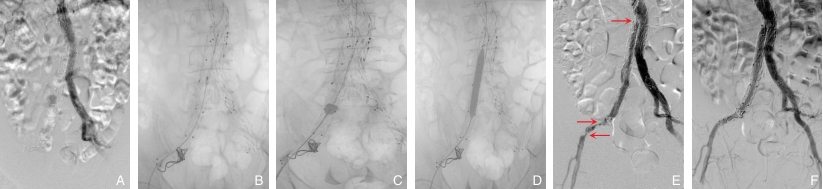

图2 编号5患者手术情况 A:术前DSA造影;B:8 F Rotarex导管减容;C:取栓导管拉栓;D:PTA;E:减容后仍有狭窄(红色箭头);F:术后DSA造影Fig.2 Surgical details of patient No.5 A: Preoperative DSA angiography; B: Debulking with an 8 F Rotarex catheter; C: Thrombectomy using a thrombectomy catheter; D: PTA; E: Residual stenosis after debulking (red arrow); F: Postoperative DSA angiography